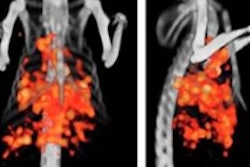

A total of 26 metastatic colon cancer patients from a single hospital were included in the study, which involved pretreatment PET/CT imaging and treatment with repeating cycles of chemotherapy. Early and late PET/CT evaluations were performed, along with peripheral blood collection at 20 days after the first treatment cycle and 20 days after the fourth cycle.

When patients were divided into responders and nonresponders, the early metabolic response category assessed by PET could predict the treatment response determined by CT in 73% of cases, with 80% sensitivity and 69% specificity, the group found. Early determination of metabolic nonresponse was significantly predictive of disease progression; nonresponders had more three times the risk of progression than responders.